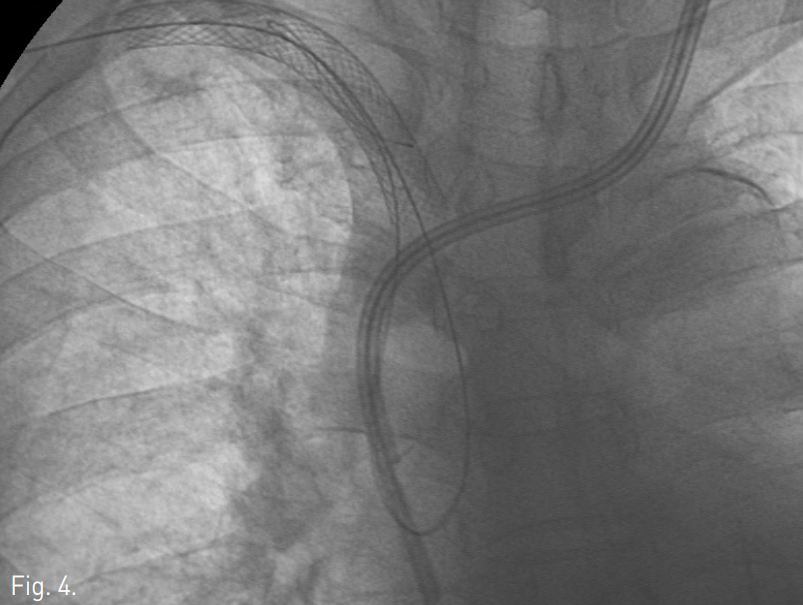

우측 동정맥루의 outflow vein을 천자하여 정맥조영술을 시행하여 쇄골하정맥 폐색을 확인한 후 5F 카테터(Cobra, Cook, Bloomington, IN, USA)와 0.035 inch 유도철사 (Terumo, Tokyo, Japan)로 폐색부위 통과를 시도하였으나 병소 부위의 저항이 심하여 실패함. 우측 대퇴정맥을 통하여 같은 방법으로 폐색부위 통과를 시도하였으나 역시 실패함. 투시와 초음파 유도하에 18G needle로 쇄골하정맥에 설치된 막혀있는 stent를 직접 천자하고(Fig. 3) 이를 통해 0.035 inch 유도철사를 삽입하여 상대정맥까지 진입시킨 후(Fig. 4), 이 유도철사를 snare catheter를 이용하여 우측 대퇴정맥 밖으로 유도함(Fig. 5). 대퇴정맥으로 나온 유도철사를 따라 직경 10mm 풍선카테터 (Cook)를 삽입하여 양측으로 나와있는 유도철사를 당겨 긴장성을 유지한 상태에서 막힌 stent내로 진입시킨 후 풍선확장술을 시행함. 풍선카테터는 제거하고 유도철사를 따라 8F guiding catheter (Cordis, Miami Lakes, FL, USA)를 일부 확장된 stent내로 진입시킨 후 양측으로 나온 유도철사를 당겨 긴장성을 유지시켜 guiding catheter가 밀리지 않게 한 상태에서 guiding catheter내로 새로운 유도철사를 삽입하여 성공적으로 막혀있는 stent를 통과시켜 상완정맥 내로 진입시킴(Fig. 6). 상완정맥 내의 유도철사를 snare catheter를 이용하여 상완 천자부위 밖으로 유도함(Fig. 7). Stent에 직접 천자하여 삽입한 첫번째 유도철사는 완전히 제거하고 상완정맥과 대퇴정맥으로 나와있는 유도철사를 당겨 긴장성을 유지한 상태에서 이를 따라 직경 10mm, 길이 4cm 풍선카테터 (Cook)를 이용하여 병소부위에 풍선확장술을 시행하고(Fig. 8), 12x80 mm Zilver stent (Cook)를 설치함. 시술 후 정맥조영술에서 쇄골하정맥은 성공적으로 개통되었고(Fig. 9), 시술 7일 후에 우측 팔의 종창은 완전히 소실되었다(Fig. 10).

Fig. 4

Radiographs show percutaneously placed guide wire in the SVC, which is pulled out through the femoral access.